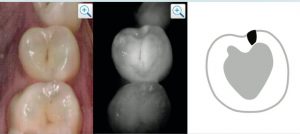

La lesione cariosa si manifesta nella sua fase iniziale come un’area biancastra dall’aspetto gessoso che rappresenta la demineralizzazione dello smalto prima ancora che questo venga penetrato dai primi batteri. In questa fase il processo infettivo è ancora reversibile ed un trattamento precoce potrebbe riportare ad uno stato di salute il dente senza necessità di dover mettere mano agli strumenti rotanti. Da qui in poi il processo comporta una perdita di sostanza corrisdpondente alla cavitazione. Tradotto i batteri penetrano all’interno dello smalto e si approfondiscono fino a raggiungere la dentina. Questa. rappresenta la parte più delicata ed è caratterizzata dalla presenza di numerosi tubuli che arrivano direttamente alla camera pulpare in cui risiedono il nervo e i vasi sanguigni del dente. A questo livello la lesione tende ad espandersi a macchia d’olio andando a sottominare lo smalto sovrastante. Lo step successivo si manifesta con i sintomi caratteristici dell’ipersensibilità al freddo e ai dolci ed è però anche lo stadio finale dell’aggressione batterica , quello in cui la polpa viene infettata e va incontro a morte. A questo punto ogni trattamento comporterà inevitabilmente la necessaria devitalizzazione dell’elemento interessato con il suo deciso indebolimento strutturale.

Poter individuare una lesione cariosa già nelle sue prime fasi diviene fondamentale per evitare di dover intervenire in modo demolitivo e sacrificare sostanza dentale. Questo è possibile al giorno d’oggi grazie all’avvento di tecnologie che consentono di individuare il processo quando ancora non ha penetrato lo smalto. Tra queste possiamo contare sul Niri (Near infrared technology), una tecnologia che sfruttando la differente rifrazione di un laser della lunghezza d’onda vicina a quella dell’infrarosso da parte dello smalto e della dentina demineralizzati consente di visualizzare i punti in cui la normale struttura dentale risulta alterata dalla carie. Un tale sistema oggi è integrato negli scanner intraorali di ultima generazione più performanti e consente già in prima visita e assolutamente senza radiazioni ionizzanti dei intercettare le lesioni curiose prima che siano visibili ad occhio nudo.

Ad aiutarci inoltre la presenza in molti studi odontoiatrici del microscopio operatorio che grazie ad ingrandimenti fino a 14X e a sistemi di illuminazione potenti e coassiali consentono di valutare al meglio ogni forma di lesione sospetta, a partire dalle whitespot spesso non intercettatili ad una visita senza ingrandimenti.